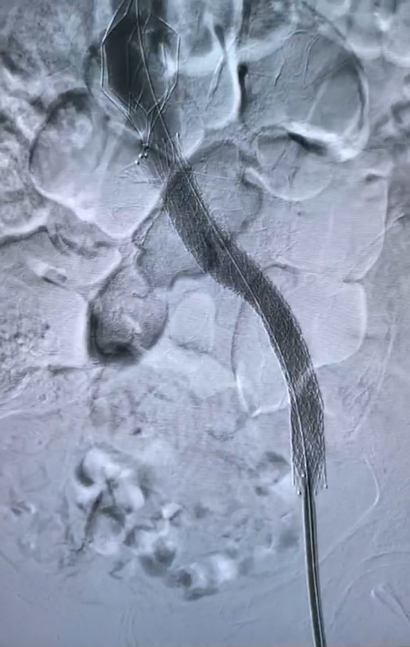

我院血管外科与介入科专家会诊后考虑患者出现股青肿表现,立即安排急诊手术。术中发现左髂静脉闭塞,股静脉逆向快速血流;左侧髂内动脉、左股动脉弥漫性动静脉瘘,前者为主,经左髂静脉回流。手术团队帮助患者开通闭塞的静脉并时刻保持血流通畅。术后第一天患者腿部就明显消肿,术后第二天腿部情况已与对侧基本一致。患者家属感叹,两年的老毛病,竟然一夜就消了。